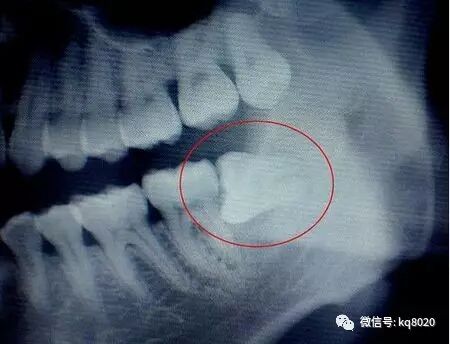

这图片是阻生智齿,也就包括横着长的智齿拔除,会比较复杂些,平常简单的拔牙就是用工具将牙齿拔掉,不用缝线,上个药就搞定啦。

如果智齿能顺利长出的话最好不过了,但有些智齿长不出来,尤其是横着的,是一项难度较大的小手术,先将黏膜切开,然后去骨....犹如剖腹产一样。拔掉后不需要镶牙,有利于身体健康,保护附近其他牙齿。